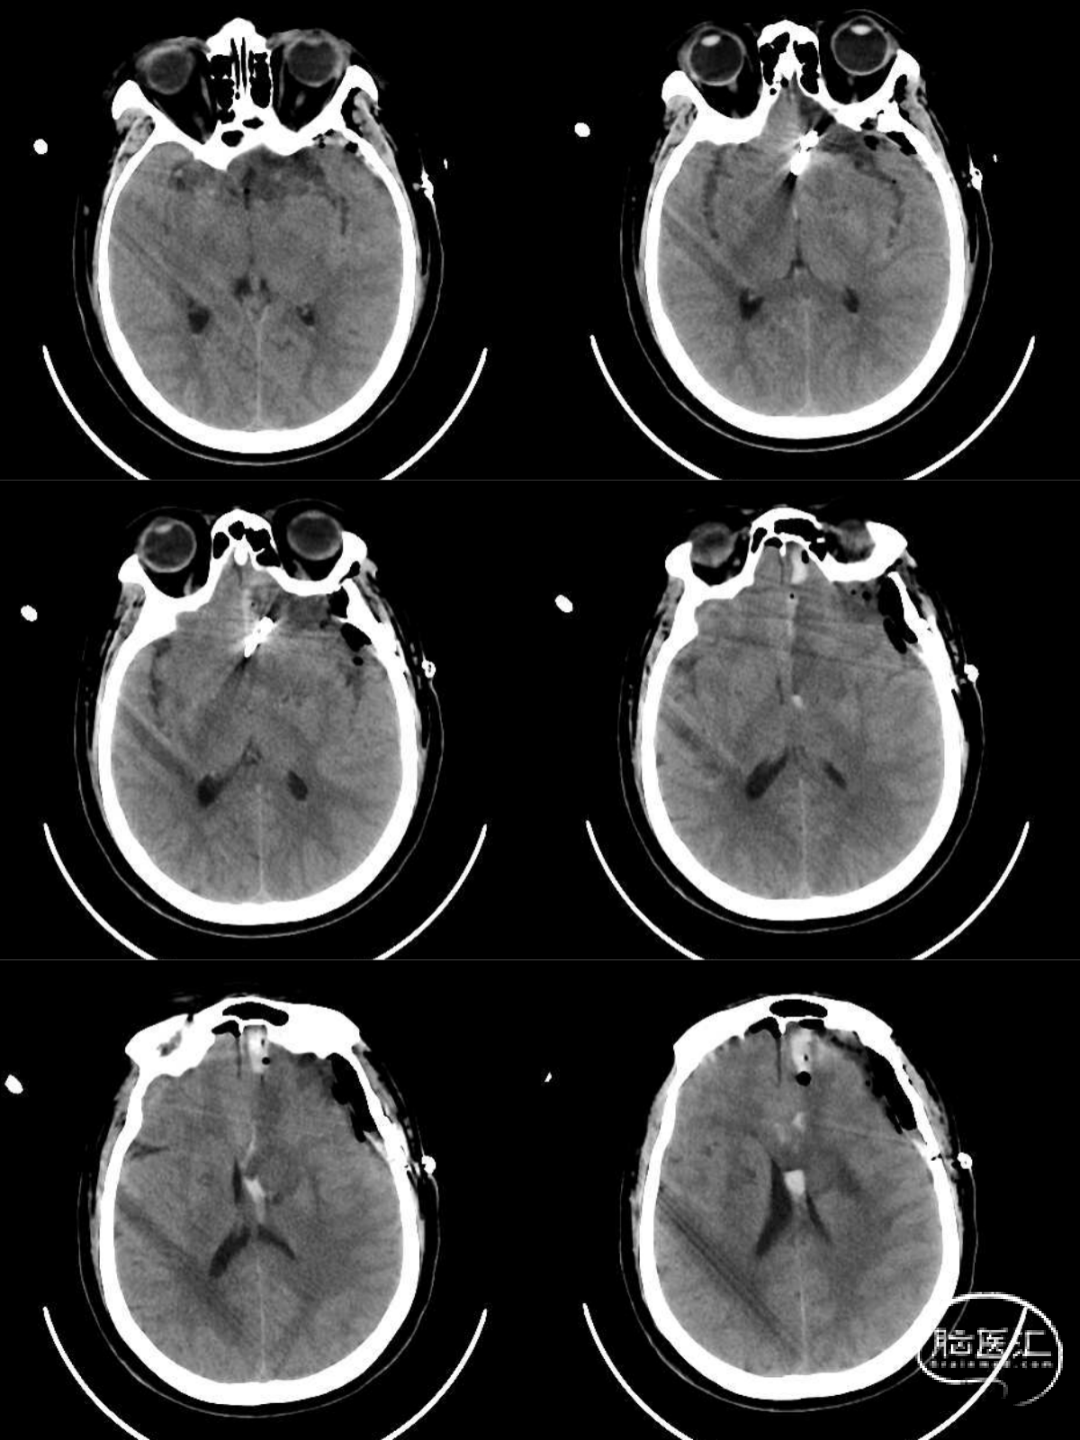

患者术后8小时意识清,四肢活动好,无明显神经功能障碍,拔除气管插管。术后5小时复查CT:颅内大部分血肿清除,颅内压不高。

图3 术后复查CT

患者术后1周出现意识模糊,并伴有暂时性尿崩症,四肢活动正常。予以加强对症抗血管痉挛、控制尿崩等治疗后逐步好转。2周复查DSA提示:动脉瘤夹闭完全,额极动脉(载瘤动脉)通畅(图4)。四肢活动好,意识清。康复出院。

图4 术后复查DSA